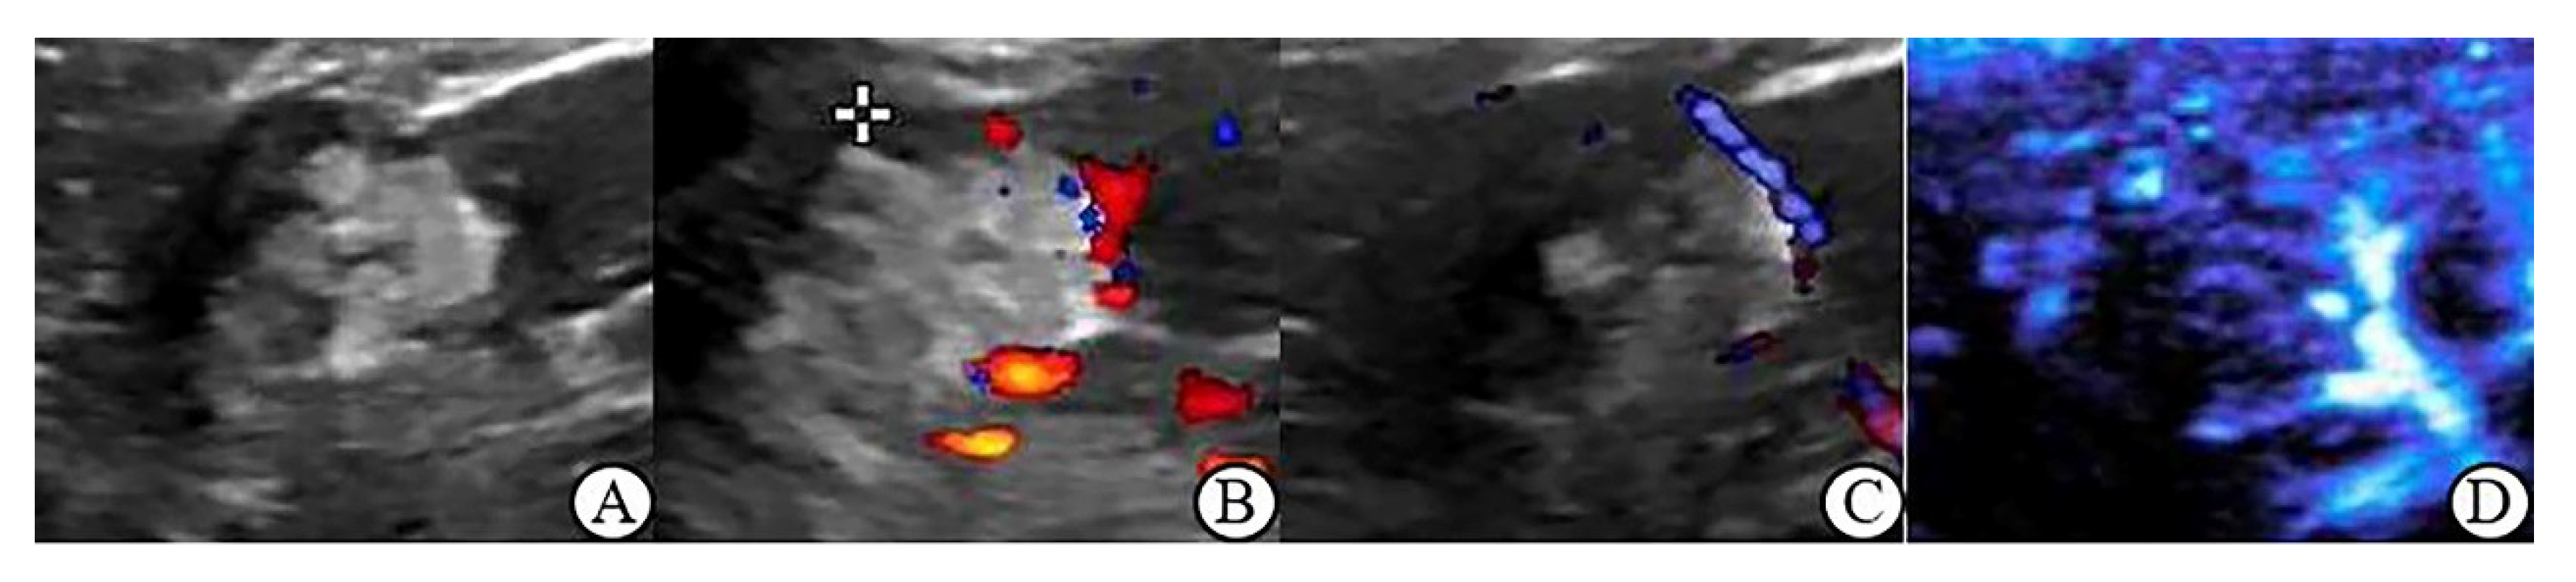

3.3. CDFI, PDI and MFI Evaluation of Blood Flow Characteristics in Benign and Malignant Renal Tumors ≤ 4 cm

3.5. Peripheral Blood Flow Characteristics of Renal Tumor in MFI Mode